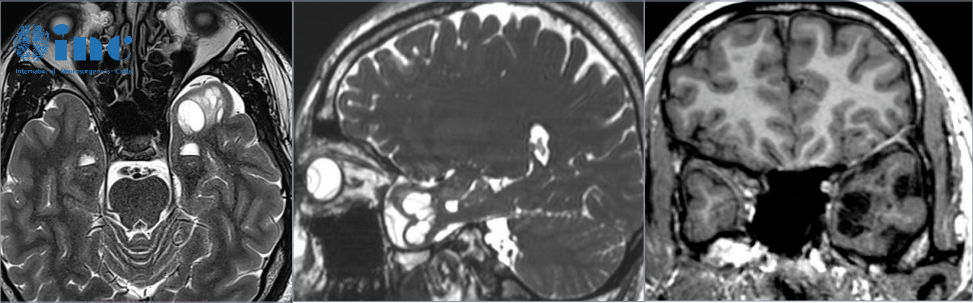

- 文章标题:左颞叶占位性病变手术还是保守治疗?可以一直等吗?